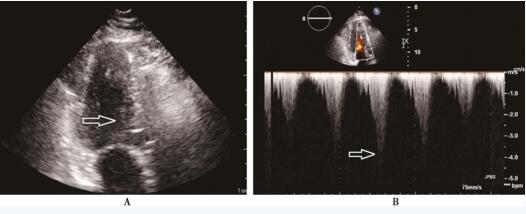

复查超声心动图:各房室大小正常;基底段室间隔凸向左心室流出道,主动脉与室间隔夹角变小,导致左室流出道狭窄,收缩期二尖瓣前叶及腱索前向运动 (SAM征);多普勒血流频谱示左心室流出道快速血流和二尖瓣反流形成双束分叉血流。诊断为S型室间隔并左心室流出道狭窄、左心室舒张功能下降、左心室收缩功能正常(图95-2、95-3)。口服β受体阻滞剂、抗血小板药物治疗后,患者好转出院。

图95-3 二维超声心动图心尖两腔切面、在心室流出道血流频谱 A:心尖两腔切面示室间隔基底部略增厚,突向左室流出道 (箭头所示);B:左心室流出道峰值血流速度达4m/s,左心室流出道压力阶差64mm Hg